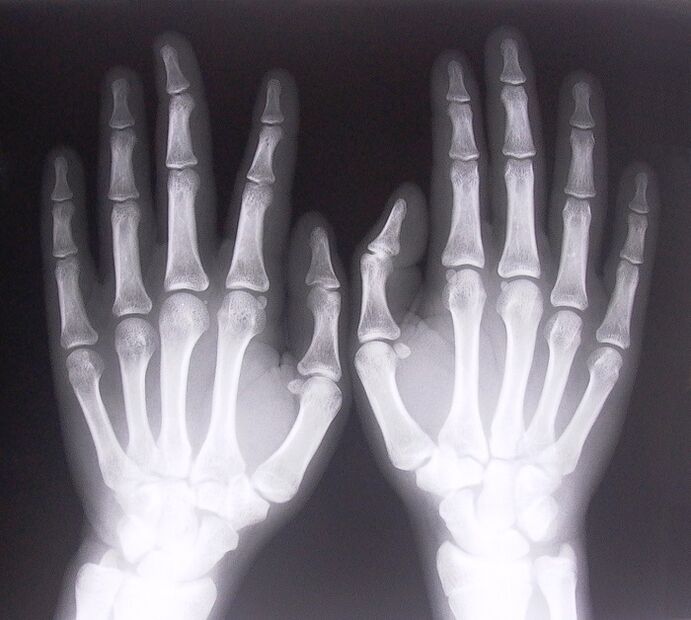

1. Veikt rentgena starus.

Rentgens kā veids, kā diagnosticēt sāpes pirkstu locītavās